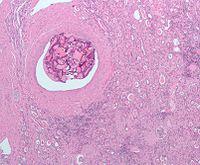

| Micrograph of the most common type of renal cell carcinoma (clear cell)—on right of the image; non-tumour kidney is on the left of the image. Nephrectomy specimen. H&E stain | |